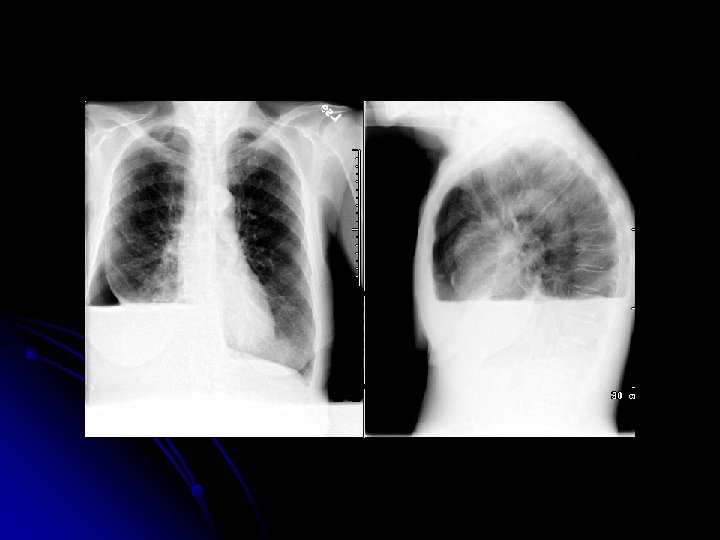

TB l 51 yaşında, işçi l Erkek l Doğum yeri: Zonguldak l

l ŞİKAYETİ Öksürük Koyu renkli balgam Efor dispnesi

l FİZİK MUAYENE: siyanoze, dispneik çomak parmak mevcut DSS: 26 (torako abdominal) OSKÜLTASYONDA bilateral inspiratuvar raller TA: 130/80 Nb: 86/dk

FVC % 55 l FEV 1/FVC %82 l Pa 02 50 mm. Hg l Pa CO 2 38 mm. Hg l

TANI ? ? ?